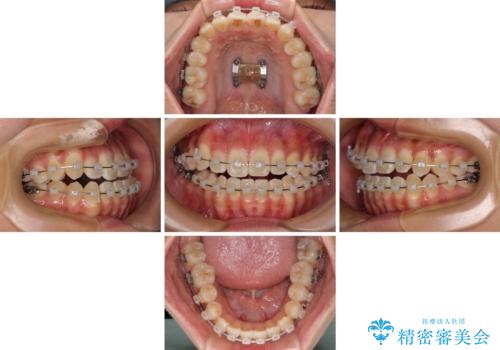

- クリアブラケット

- 1年6ヶ月

- 10-30回

上顎歯列が狭窄していたため、急速拡大装置により上顎骨を側方に拡大し、その後ワイヤー装置にて矯正治療を行うこととしました。

急速拡大装置で上顎骨を十分に拡大できたことで、非抜歯で八重歯を歯列に納めることができました。